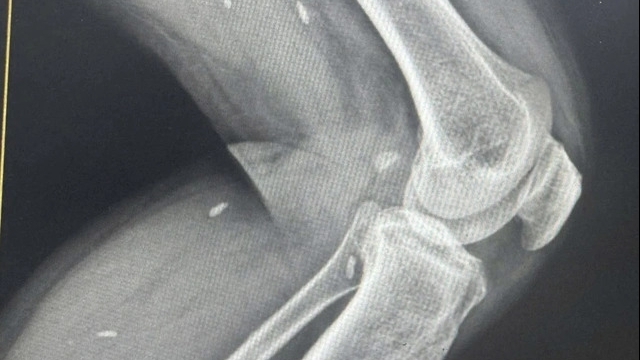

Sau khi đồng tử có dấu hiệu co lại, các bác sĩ quyết định thực hiện hồi sức nâng cao với các biện pháp: thở máy, lọc máu liên tục và đưa bệnh nhân vào hệ thống hạ thân nhiệt chỉ huy nhằm bảo vệ chức năng não bộ. Hiện bệnh nhân đang được điều trị tích cực tại khoa Cấp Cứu.

| Hiện bệnh nhân đang được điều trị tích cực tại khoa Cấp Cứu (Ảnh: Bệnh viện Bệnh Nhiệt đới Trung ương) |

Ths. BS Lê Sơn Việt, Bệnh viện Bệnh Nhiệt đới Trung ương cho biết: “Đây là trường hợp có nguy cơ di chứng thần kinh rất nặng nề sau ngừng tuần hoàn. Tuy nhiên, hiện tại bệnh nhân đang có tiến triển nhất định, đồng tử đã về bình thường và có phản xạ, đã cắt thuốc vận mạch và ngưng lọc máu. Chúng tôi sẽ giảm dần thuốc an thần và đánh giá tình trạng ý thức trong những ngày tới”.